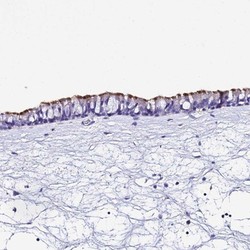

- Main image

- Experimental details

- Immunohistochemistry-Paraffin: TMEM117 Antibody [NBP1-94078] - Staining of human nasopharynx shows strong membranous positivity in respiratory epithelial cells.